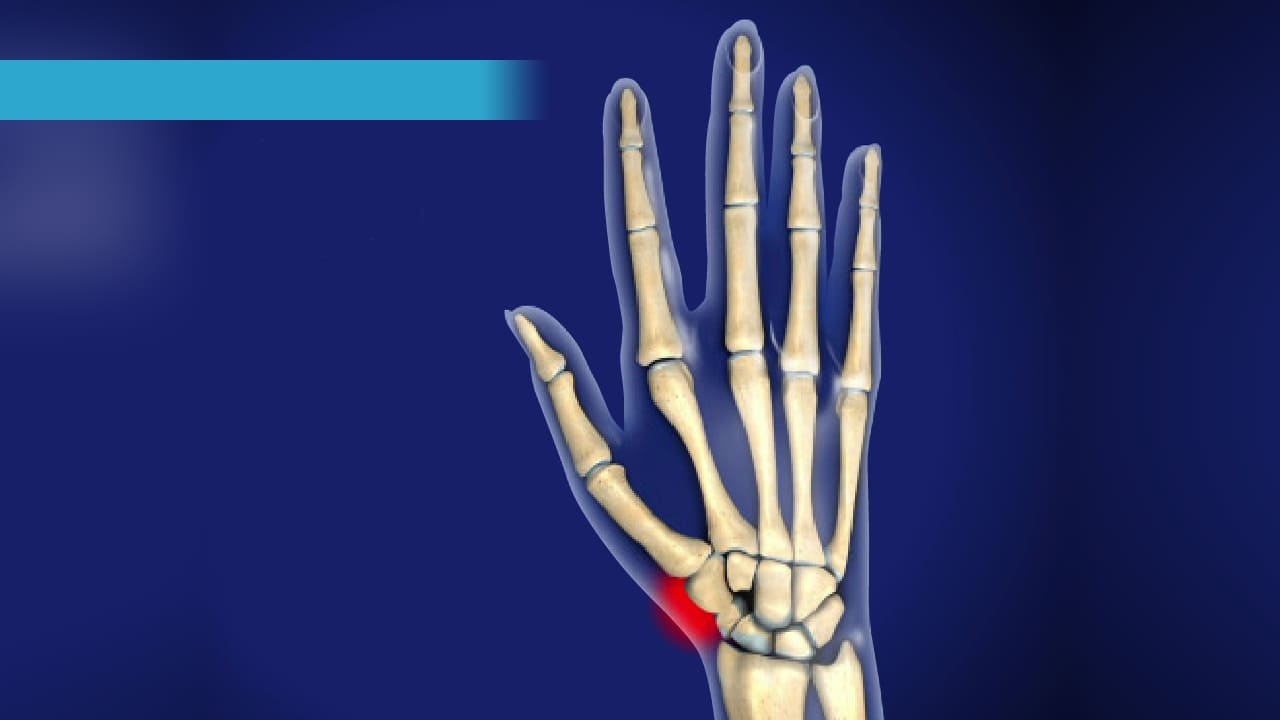

Wrist Fractures

Wrist Scaphoid Fractures

Carpal Injuries

Wrist Scaphoid Nonunion